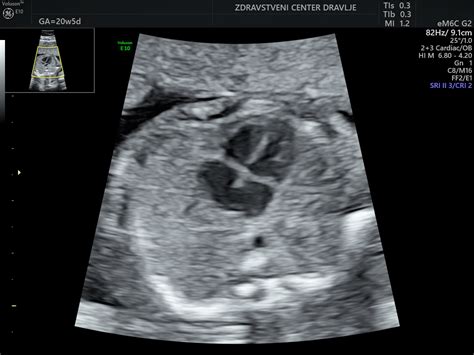

Prezgodnji porod predstavlja enega najpomembnejših izzivov v sodobni perinatologiji, saj predstavlja tveganje tako za novorojenčka kot za starše. Ko se porod zgodi pred dopolnjenim 37. tednom nosečnosti, govorimo o prezgodnjem porodu. Vendar pa so izzivi in posledice bistveno večji, če se otrok rodi v zgodnejših fazah nosečnosti, kot je na primer 30. teden. Ta članek bo podrobno raziskal vzroke, potek in posledice prezgodnjega poroda v 30. tednu nosečnosti, pri čemer bomo izhajali iz strokovnih izkušenj in osebnih zgodb.

Nosečnost, ki traja običajno 40 tednov od prvega dne zadnje menstruacije, je ključen proces za popoln razvoj ploda. Nedonošenčki so vsi otroci, ki se rodijo pred dopolnjenim 37. tednom nosečnosti. Vendar pa je ključna razlika med nedonošenčkom, rojenim na primer v 36. tednu, in tistim, ki se rodi ob 30. tednu nosečnosti. Zakonodaja postavlja minimalno mejo nosečnosti na 22 tednov; otrok, rojen pred to mejo, se šteje za splav, po tej meji pa za porod.

Otroci, rojeni pred 30. tednom nosečnosti, imajo manj možnosti za kakovostno preživetje brez posledic. Njihovi organi, zlasti pljuča, so pogosto nezreli, kar vodi v dihalno stisko in povečano nagnjenost k hudim okužbam, ki lahko vodijo v kronične pljučne bolezni. Možni zapleti vključujejo tudi možganske krvavitve s posledično motorično in senzorično prizadetostjo.

Otroci, rojeni v 30. tednu, so praktično štiri mesece prezgodaj. Večini teh otrok gre dobro in napredujejo, zelo redkokateri umre. Vendar pa je pri nekaterih mogoče, da imajo kakšno posledico prezgodnjega rojstva. Večina posledic je v smislu motenj v motoričnem razvoju, nekaj tudi v duševnem razvoju. Nekateri so lahko slabovidni, drugi imajo lahko posledice zaradi zdravljenja z zdravili, kot je gluhost. Pri najmanjših, rojenih pred 28. tednom, starše pripravijo na možne posledice, medtem ko naj bi pri tistih, rojenih po 28. tednu, zdravljenje in poznejši razvoj praviloma potekala v redu.